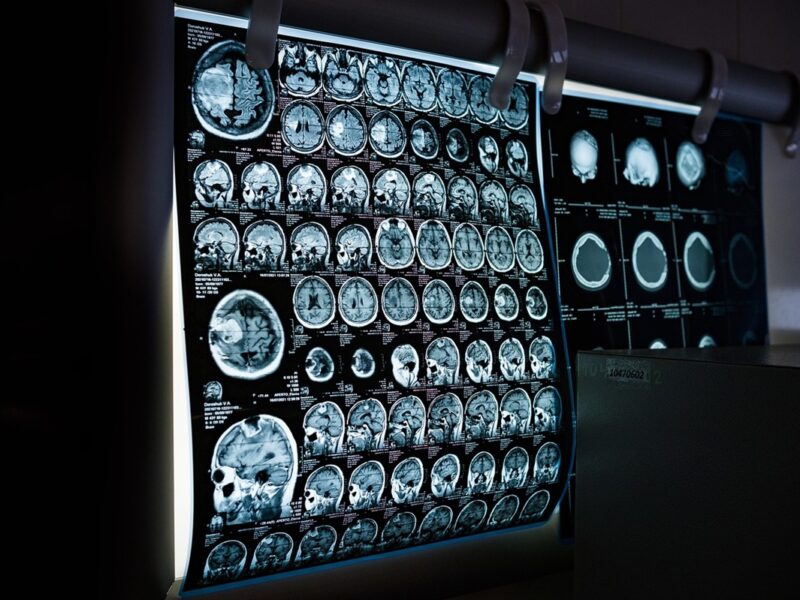

У 28-річної Енні Седорік у США протягом двох років виявили рідке гормональне захворювання – акромегалію, спричинене пухлиною гіпофіза. Жінка почала відчувати біль у щелепі, деформації обличчя, проблеми зі здоров’ям, але численні лікарі довго не могли встановити діагноз. Після операції на щелепі і видалення пухлини вона потрапила в реанімацію через ускладнення, але наразі веде активний спосіб життя, займається спортом, проте постійно переживає через можливий рецидив захворювання. Енні проходить регулярні обстеження, адже життя з невидимою хворобою та постійним болем для неї стало складним випробуванням.